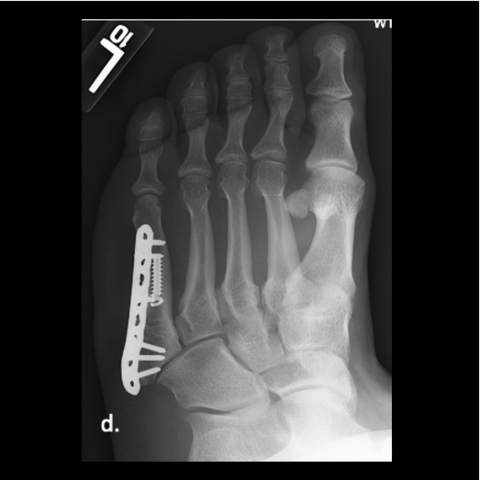

Figure 6c

Figure 6c. Plating of the fracture since screw fixation was not possible, and the patient refused external fixation for a second time.

-

Figure 6d

Figure 6d. Plating of the fracture since screw fixation was not possible, and the patient refused external fixation for a second time.

Figure 6e

Figure 6e. Plating of the fracture since screw fixation was not possible, and the patient refused external fixation for a second time.